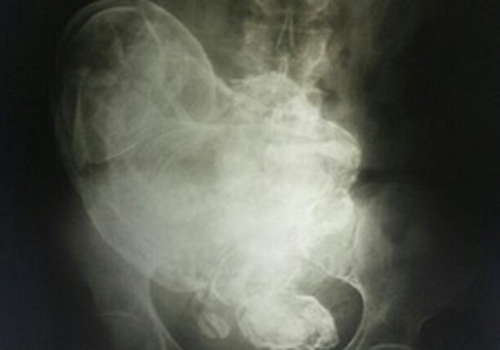

Segundo a ginecologista, o corpo da idosa encontrou uma forma de conviver com o feto | Foto: Reprodução/Internet

Pela ultra-som não foi possível ver o feto. Nós fizemos um raio-x. Pelo exame é possível ver o rosto, os ossos dos braços, das pernas, as costelas e a coluna. Algumas partes estão "borradas", estão em uma fase de calcificação e tiveram o aspecto modificado. É provável que o feto tenha morrido na 20ª semana, no máximo na 28ª", explicou Gesneria.